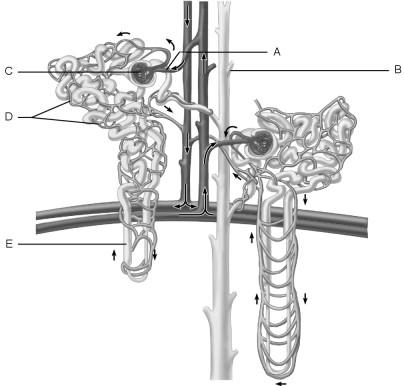

Afferent arteriole.

A

In the kidneys, the countercurrent mechanism involves the interaction between the flow of filtrate through the nephron loop of the juxtamedullary nephrons (the countercurrent multiplier) and the flow of blood through the limbs of adjacent blood vessels (the countercurrent exchanger). This relationship establishes and maintains an osmotic gradient extending from the cortex through the depths of the medulla that allows the kidneys to vary urine concentration dramatically.

TRUE or FALSE

TRUE

Cells that are most affected by ADH.

C

Medulla of the kidney.

E

Glomerulus.

C

Is composed of simple squamous epithelium.

A